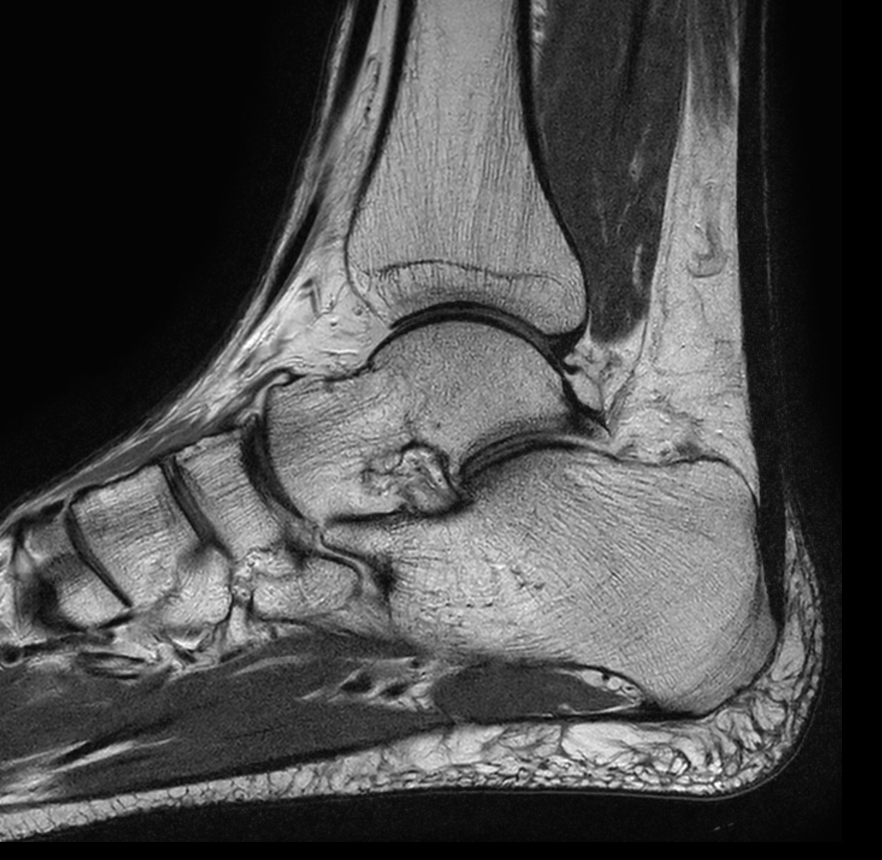

Ankle imaging with the dS 16ch FootAnkle coil

• Clinical Application